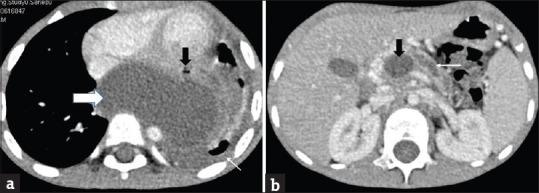

Mediastinal pancreatic pseudocyst (MPP) is an infrequent complication of acute pancreatitis in children. A contrast-enhanced computed tomogram (CECT) of the chest and abdomen can aid in diagnosing pleural effusion and MPP. We describe a child with MPP in whom a transcutaneous computed tomogram-guided external drainage was curative. The case is being presented, and the relevant literature is highlighted in view of rarity of this entity.

纵隔胰腺假性囊肿(MPP)是儿童急性胰腺炎罕见的并发症。胸部和腹部的增强计算机断层扫描(CECT)有助于诊断胸腔积液和MPP。我们描述了一名患有MPP的儿童,经皮计算机断层扫描引导下的外引流对其有效。鉴于该病症的罕见性,现展示该病例并重点介绍相关文献。